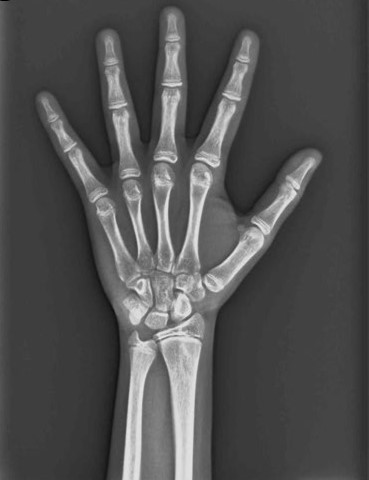

Radiografía Carpal

Es una herramienta fundamental para evaluar el desarrollo óseo, ofrece una visión crucial del patrón de crecimiento del paciente, ayudándote a tomar decisiones informadas y a personalizar tu tratamiento.